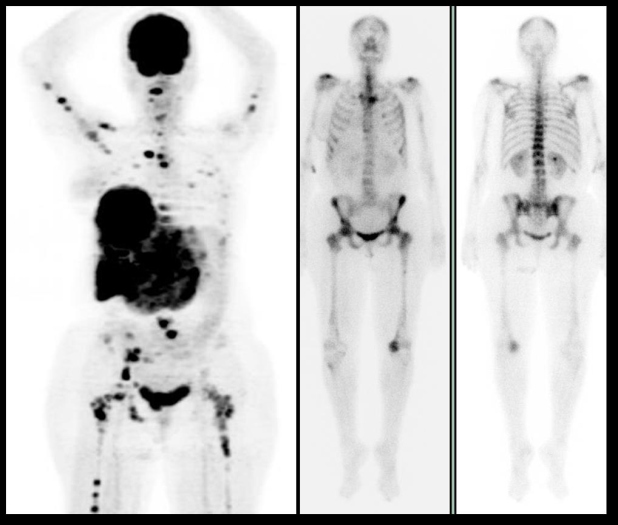

Figura 3.

Figura 3. Paciente de 63 años con diagnóstico reciente de cáncer de mama, con patología articular inflamatoria de larga evolución. El gammagrama óseo (imágenes de la derecha) pone de manifiesto los cambios inflamatorios en grandes articulaciones, pero no hace evidentes lesiones en pelvis vistas en el PET (izquierda). En escápula izquierda se aprecia claramente una lesión que puede confundirse con etiología inflamatoria de hombro.